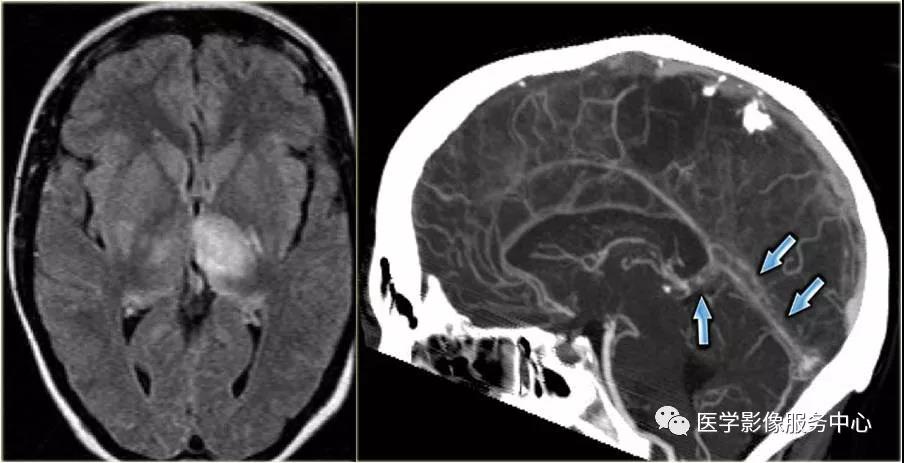

Flair序列显示左侧丘脑及右侧基底节区高信号影,双侧异常需要考虑大脑深静脉血栓的可能性,CT增强矢状位显示直窦和大脑大静脉的充盈缺损(蓝箭头)